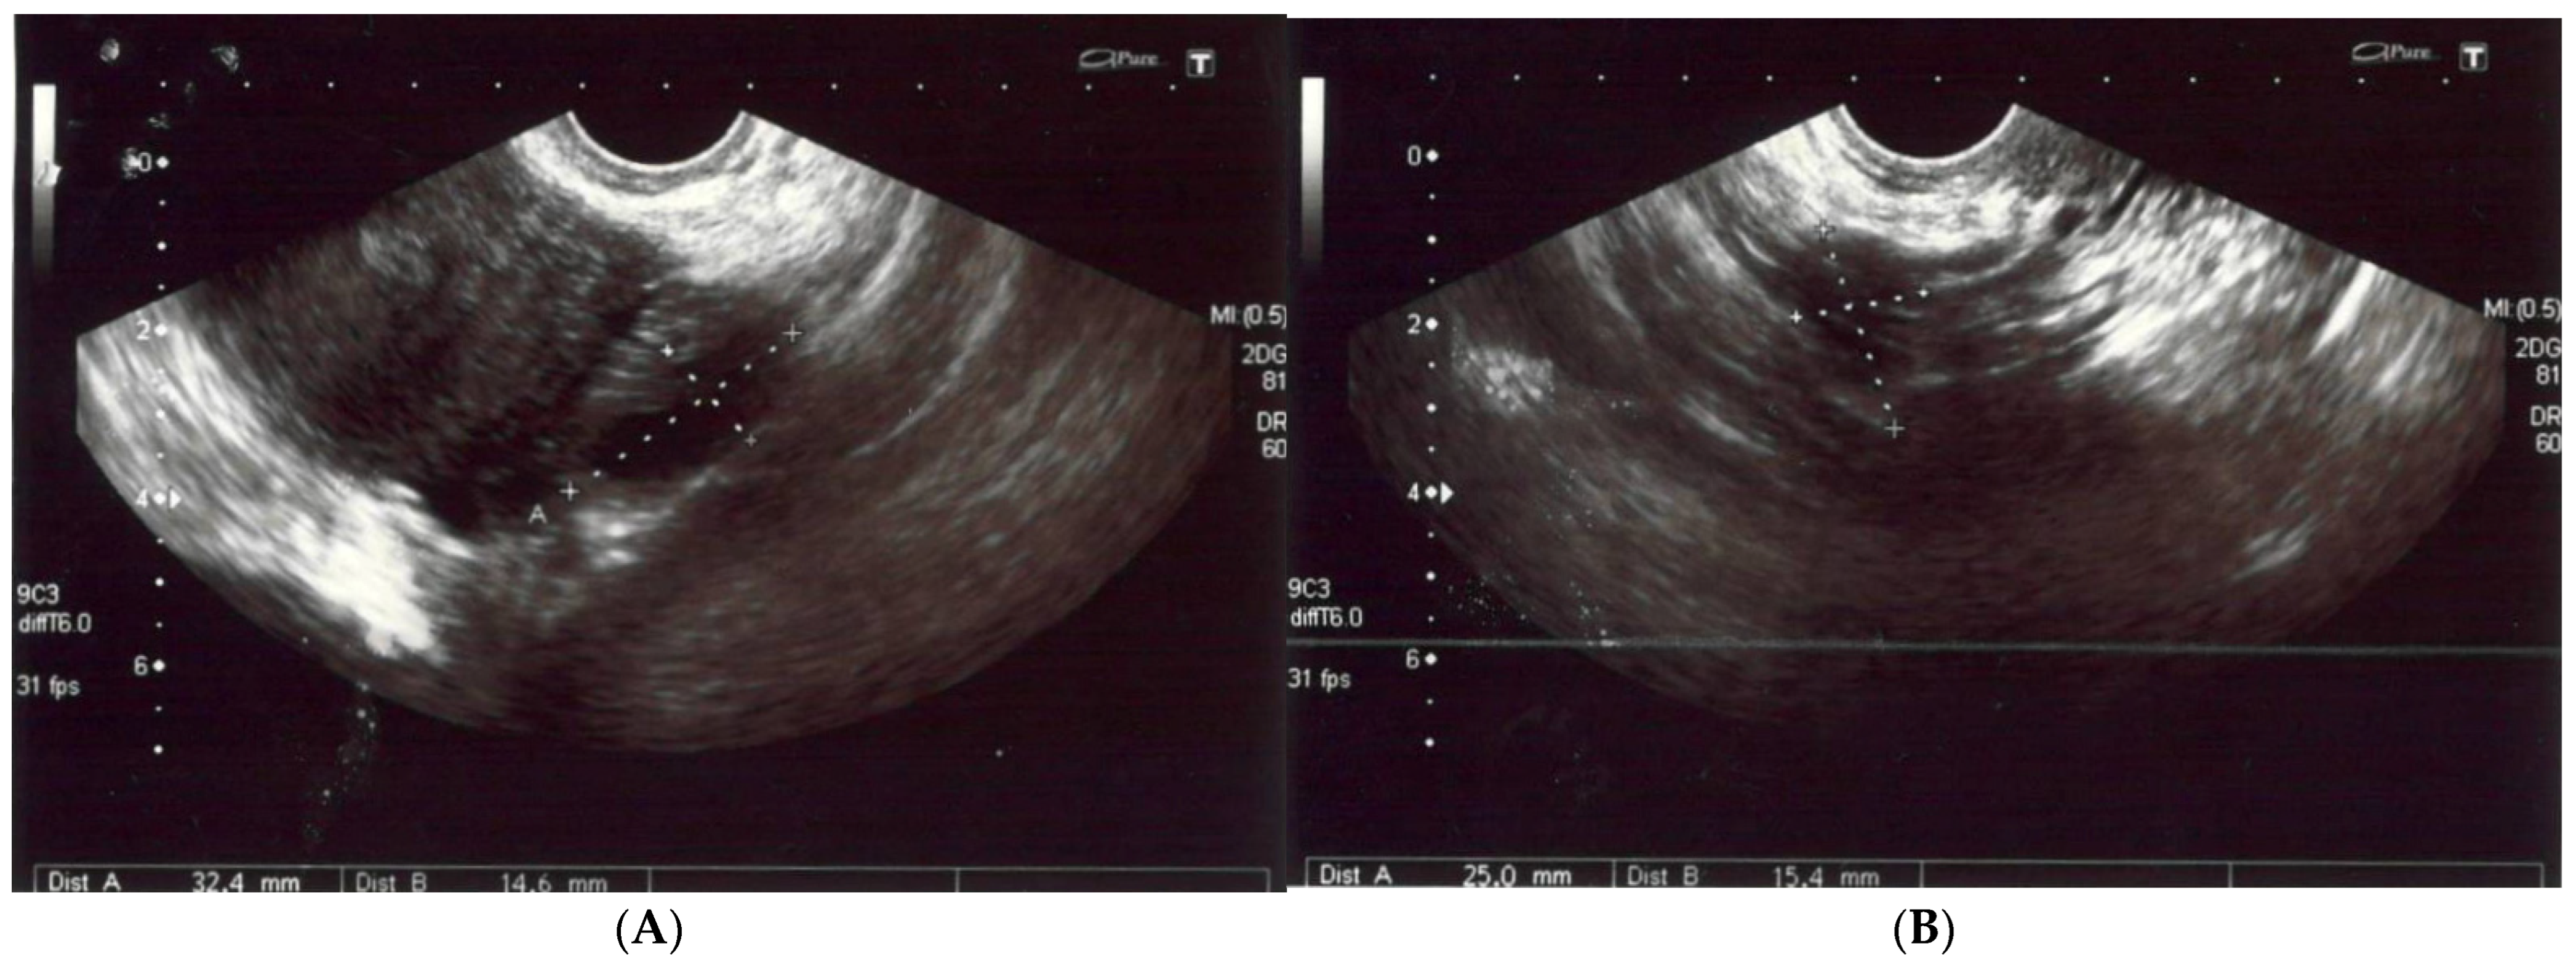

The patient reported nonspecific signs of fatigue and impaired concentration. The magnetic resonance imaging (MRI) of the head revealed a 16 × 18 × 12 mm tumor in the region of the clivus. On T1-weighted imaging, the lesion was isointense and peripherally enhanced after contrast administration. The borders of the lesion were hyperintense while the main part was isointense (Figure 2A). On T2-weighted imaging, the lesion was isointense as well (Figure 2B). On computed tomography (CT), the tumor had smooth outlines with a hypersclerotic rim. It was located centrally and did not show any penetration into the sinuses (Figure 2C). In diffusion-weighted imaging (DWI), no signals of recent ischemic changes were found. The radiology images were also nonspecific and suggested chordoma or fibrous dysplasia.

Figure 2.

(A) The magnetic resonance postcontrast T1-weighted sagittal image, demonstrating the isointense lesion with hyperintense borders (arrow). The image suggested chordoma or fibrous dysplasia (B). The magnetic resonance T2-weighted dark fluid sagittal image, showing the isointense clival lesion (arrow) (C). The computed tomography image, showing the centrally located lesion with a hypersclerotic rim (arrow). The tumor did not infiltrate the sphenoid sinuses.